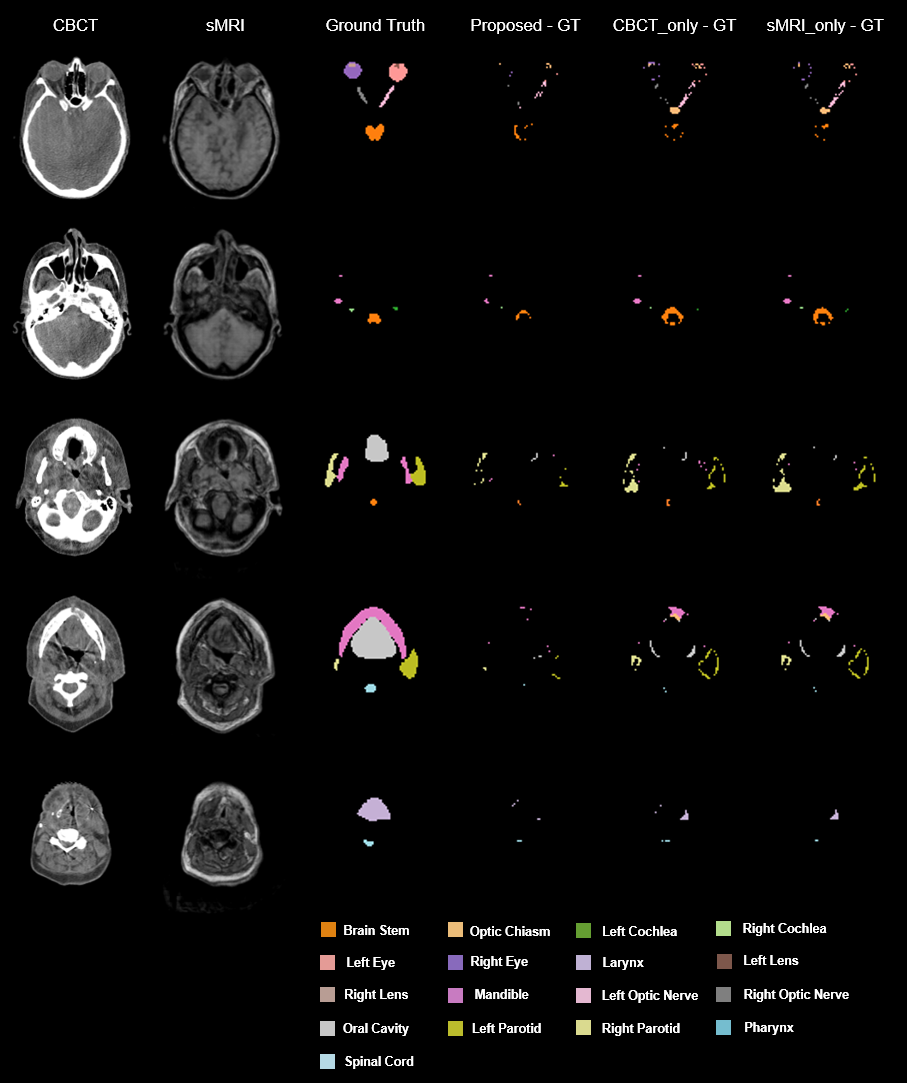

For comparison, we conducted all the experiments on both the proposed method (CBCT+sMRI), the approach using the same network (dual pyramid networks) excluding cycleGAN but only taking CBCT as inputs (two channels of CBCTs were used as inputs of the DPN without synthetic MRI), which we named as CBCT_only, and the method using dual pyramid networks but taking sMRI for the two channel inputs, which we named as sMRI_only approach. Figure 3 shows the results from one patient. Five different transverse slices are shown in five rows. The leftmost two columns are respectively CBCT and sMRI images, followed by the next four columns respectively showing the ground truth, the discrepancies of the proposed method predicted, CBCT_only predicted, sMRI_only predicted contours referring to the ground truth. Figure 4 shows the three orthogonal views (axial, sagittal, and coronal) of another case. The rows from left to right show the CBCT, sMRI, the ground truth, the differences between the ground truth and the predictions by our proposed, CBCT_only, sMRI_only methods respectively. Qualitatively investigating on the images in Figures 3 and 4, we can see, the predicted contours from our proposed method have less discrepancies with the ground truth than either CBCT_only or sMRI_only method, attribute to the strength of combining the complementary features extracted from CBCT and synthetic MRI images.

[Uncaptioned image]

Fig. 3. An illustrative example of the benefit of our proposed method compared with CBCT_only, and sMRI_only methods. sMRI, synthetic MRI; Proposed – GT, the discrepancy between the proposed predicted contours and the ground truth; CBCT_only – GT, the difference between CBCT_only predicted contours and the ground truth; sMRI_only – GT, the discrepancy between sMRI_only prediction and the ground truth.